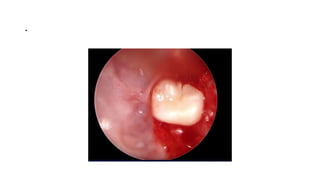

Bulbar Transconjuctival Orbitotomy

• .

Bulbar conjunctival incision

Bulbar transconjuctival incision

Cavernous Hemangioma